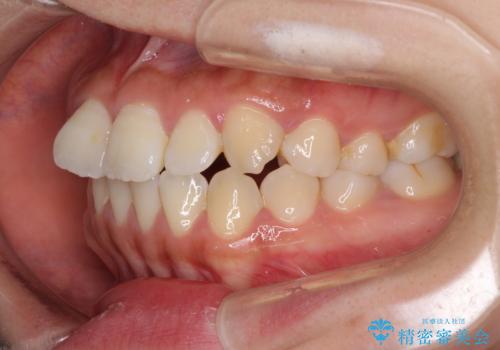

- 上顎歯列と下顎前歯の叢生を気にして来院された患者様です。

上顎からワイヤー矯正を開始し、終了間際から下顎前歯の叢生解消するよう計画しました。

部分矯正でしたが、咬み合わせに違和感が出ることなく気になる部分を改善させることができました。